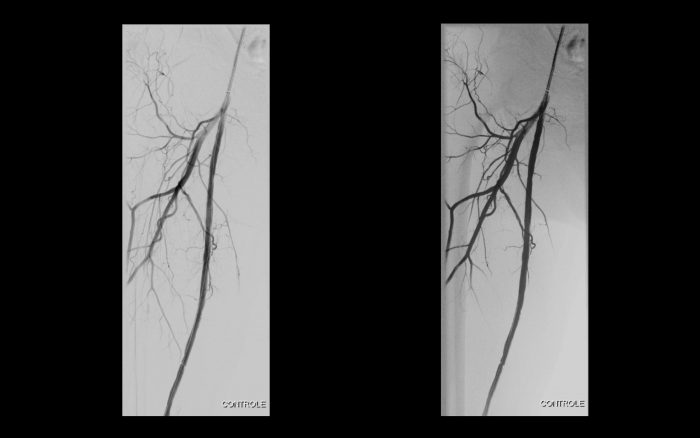

Paciente com história de claudicação dos membros inferiores para curtas distâncias, já submetido a angioplastia do membro inferior direito, retorna ao serviço com piora dos sintomas no lado esquerdo, sem lesão trófica (Rutherford 3)